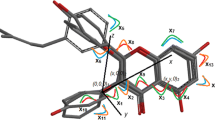

The biological data used in this article are 76 aromatase inhibitor molecules of long-chained diarylalkylimidazole and diarylalkyltriazole molecule skeletons (Karjalainen et al., 2000). The basic structural skeleton of the compounds used in this study is given in Fig. 1. The detailed structural features and biological activity of these compounds are listed in Table S1 of the supplementary section. The biological activity data and the concentration of 50 % inhibition (IC50) were converted to logarithmic scale (pIC50) and then used for subsequent QSAR analysis as dependent variables.

Previous studies (Jones et al., 1990; Okada et al., 1996, 1997) revealed that inhibitory potency for aromatase depends on the position and number of nitrogen atoms in the heterocycles, which can be due to polar and charge interactions. We investigated the HOMO shape of imidazole derivative and corresponding triazole derivative (Fig. 3). It appears that the molecular orbital involved in the eventual coordination bond with the iron atom is located on the imidazole ring of molecule 68, but it is spread over the phenyl rings in the case of molecule 69. The relative unavailability of the nitrogen electron pair of the latter compound explains the low inhibitory activity of the 1,3,4-triazole-1yl-substituted derivatives. However, there are several aromatase inhibitors drugs, possessing a triazole moiety, which are very potent, e.g., vorozole, letrozole. In fact, Lange et al. (1993) demonstrated that the replacement of the imidazole group by a triazole moiety results in lower in vitro inhibition and higher in vivo activity. It has shown that the increased in vivo activity of triazoles compared with imidazoles is due to increased metabolic stability of the triazole derivatives.

Karjalainen et al. found that the substitution of the 1-position of imidazole with the diarylalkyl moiety preserved some activity (e.g., see compound 22 with IC50 of 16 μM), whereas the substitution of the 2-position of imidazole reduced activity radically (for example, 2-(4,4-diphenylbutyl)-2H-imidazole with IC50 over 1000 μM). The difference in potency of the molecules can be explained partly by difference in the HOMO shape of the molecules (Fig. 4). In high-potency molecule, the HOMO orbital is mainly located over the imidazolyl ring, whereas in the low potency molecule, the HOMO orbital is distributed over other parts of the molecules (Fig. 5).